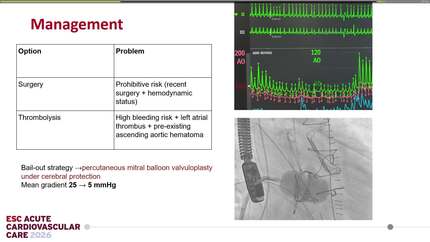

Rescue TTVR with a new-sized EVOQUE valve following transcatheter edge-to-edge repair